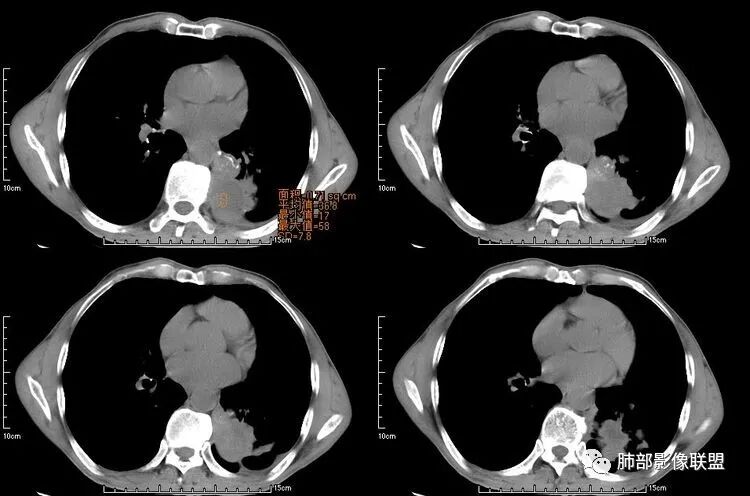

患者老年男性,咳嗽、咳痰、痰中带血伴胸闷2月余。长期大量吸烟史。查肝肾功能、血糖、血脂、心肌酶、电解质、血沉、C反应蛋白、抗“O”、类风湿因子、抗核抗体谱无明显异常。肿瘤标志物提示NSE、CYFRA21-1稍升高。胸部CT:肺气肿背景,左肺下叶后基底段不规则肿块影,见支气管截断,内见大片状低密度区及部分血管影,增强轻度强化,远端空洞形成。双肺多发不规则实性结节影、见毛刺、胸膜牵拉及血管集束,结节内见空洞形成,部分可见血管影,多位于胸膜下。双肺见多发肺大泡。综合考虑左下肺恶性病变并双肺转移。鳞癌或淋巴瘤可能。鉴别血管炎性病变及真菌感染。

左肺下叶团块病灶,有明显张力,增强后病灶内部有可疑延迟强化,看不清楚病灶与支气管的关系,应该支气管受压阻塞了,双肺多发胸膜下小结节,病灶小结节病灶有平行胸膜生长的表现,部分小结节厚壁,部分薄壁,,还有一部分有内容物,这需要两元论,左肺下叶肺癌(腺癌)伴转移,同时合并真菌感染。

液化,而不像坏死,是有强化的;这个里面似有液平。说明里面有分泌粘液?

无发热,其他慢性细菌先不考虑,有的低毒的,但是结节形态还是比较不规则的,分布也是比较随机,更像原发病灶。真菌方面,结节没有融合,坏死也是液化坏死,不符合隐球菌,曲霉不符合IPA,慢性吸入的也少见。结核没有树丫,不考虑。鉴别主要是GPA,和肺癌。GPA不支持点是皮肤,肾脏没有累及,ANCA不支持。。。肺癌主要是腺癌和鳞癌转移。比较支持的是淋巴结肿大,和左下肺的主病灶,支气管堵塞和异常强化。还有分叶,局部膨隆。可以建议支气管镜检测。

本病例左肺下叶肿块,有深分叶、毛刺、胸膜牵拉凹陷、支气管截断及纵隔内淋巴结肿大等征象,都均支持病灶为恶性,如腺癌,而且叶间裂的多发结节也提示是腺癌来源可能大;双肺多发结节、肿块,大部分病灶有分叶、毛刺及胸膜凹陷的恶性征象,与原发肿瘤本身的性质有关,所以应该与左肺下叶肿块同源,而且双肺多发病灶内空洞也具有多样性;